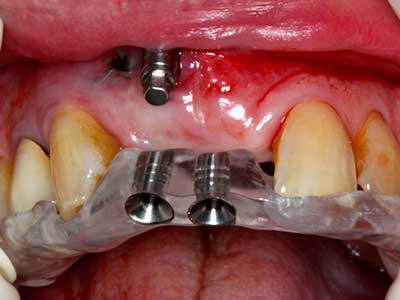

Костната тъкан е не само минерализирана структура, тя съдържа и съществено количество колагенови влакна. Това означава, че тя има не само добра компресивна сила, но и известна степен на гъвкавост, която може да се възприеме като предимство при извършване на костна аугментация. В класическата процедура по разширяване чрез костно разделяне, атрофиралият алвеоларен гребен е разделен надлъжно и внимателно разширен след достигане на подходящата остеотомна дълбочина (Фиг. 13-16), в идеалния случай без допълнително отстраняване на периостеума (Brugnami, Caiazzo et al. 2014, Stricker, Fleiner et al. 2014). Системите с винт и пластини с увеличаване на разстоянието при разширяване са доказали ефективността си при разделяне на двете костни ламели, оставайки под прага на фрактурите. В общи линии, оставащата ширина на костта от поне 3–4 mm е задължителна (Chiapasco, Zaniboni et al. 2006), за да се гарантира добра гъвкавост и достатъчно костно покритие за бъдещото поставяне на импланти. Ако е необходимо, вертикалната остеотомия на едната или двете страни може да подобри гъвкавостта. Комбинацията с допълнителни техники за аугментация, особено в букалната страна, е описана като алтернатива на класическата техника.

Процедурата по разделяне е атравматична и няма голяма загуба на пространство, използвайки пиезотриони, и няма значителна разлика между импланти в разделени челюсти и импланти в алвеоларния гребен без костен дефицит (Chiapasco, Zaniboni et al. 2006, Danza, Guidi et al. 2009). Въпреки това, важно е да има достатъчно и продължително охлаждане, особено при ограничено и дълбоко разделяне, за да се избегне термичен стрес в апикално-остеотомните зони.